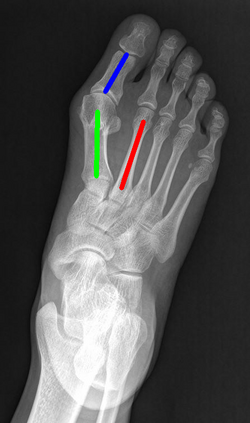

Angular measurements is essential to make a resonable treatment for Hallux valgus (HV), a common forefoot deformity. However, it still depends on manual labeling and measurement, which is time-consuming and sometimes unreliable. Automating this process is a thing of concern. However, it lack of dataset and the keypoints based method which made a great success in pose estimation is not suitable for this field.To solve the problems, we made a dataset and developed an algorithm based on deep learning and linear regression. It shows great fitting ability to the ground truth.